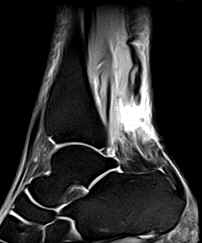

• Complete Rupture:

• There is discontinuity of the tendon (unless the tendon edges are overlapping) with intervening fluid, fat or hemorrhage.

• The proximal fragment is retracted with fraying. The distal fragment is lax and buckled. Sagittal images help in ascertaining the distance between the two fragments.

• Hemorrhage, edema and inflammation may be seen in the peritendinous soft tissues. There may be fluid collection in the paratenon anterior to the tendon.